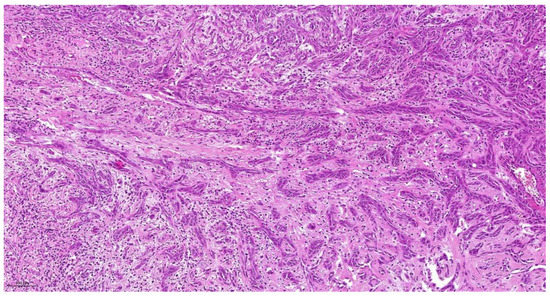

| Tumor Budding * (TB) | No tumor budding | Score 1 |

| 1–5 tumor buds/HPF | Score 2 | |

| >5 tumor buds/HPF | Score 3 | |

| Cell Nest Size (CNS) | >15 cells per nest 5–15 cells per nest 2–4 cells per nest | Score 1 Score 2 Score 3 |

| single cell invasion | Score 4 | |

| Cellular Dissociation Grade (CDG) | Sum TB + CNS = 2–3 Sum TB + CNS = 4–5 | CDG-1 CDG-2 |

| Sum TB + CNS = 6–7 | CDG-3 |